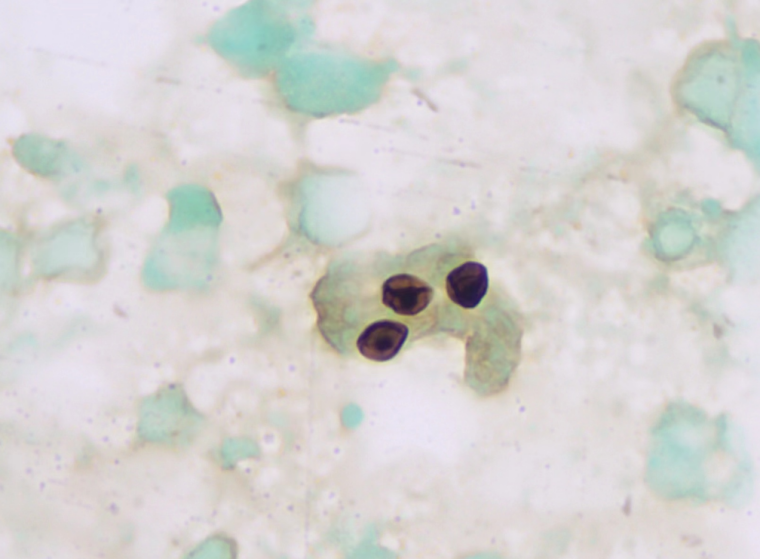

在西安区域医学检验中心临床微生物实验室与各级医疗机构的合作中,不时需要使用六胺银染色进行检测。要了解六铵银染色的重要性,先要了解一下该染色方法的唯一主角:肺孢子菌。